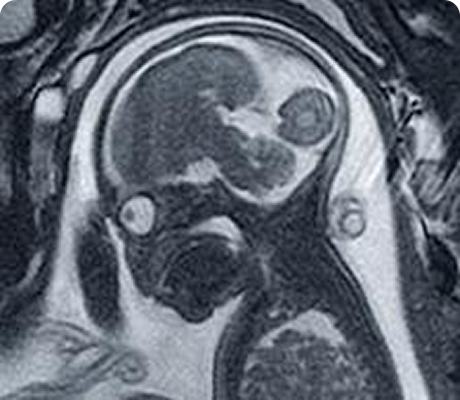

En la Clínica de Medicina Materno Fetal del Hospital Angeles Lomas, ofrecemos detección oportuna de enfermedades en el feto y complicaciones en la madre, mediante estudios de genética e imagen con tecnología avanzada y médicos altamente especializados.

"Durante el embarazo, los ultrasonidos son una parte fundamental del control prenatal. Nos permiten observar el desarrollo del bebé, identificar posibles complicaciones a tiempo y tomar decisiones médicas informadas para cuidar tu salud y la de tu bebé."